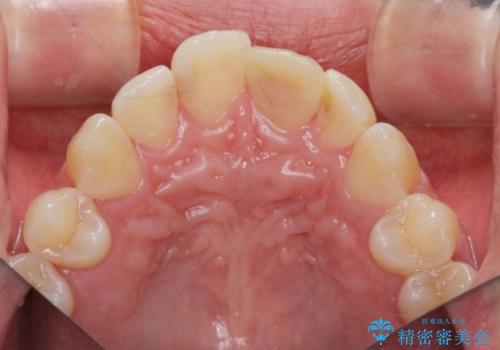

前歯の変色を改善するセラミッククラウン治療

- 以前に前歯を強打し、変色してきた前歯の審美性の改善を希望されて来院されました。

X線検査の結果、変色をきたしている歯は根尖病変が存在し、神経が失活している状態でした。

根管治療を行ったのち、セラミッククラウンで審美性を改善していきます。

歯科技工士との綿密な打ち合わせで、非常に自然なセラミッククラウンを作製することができました。